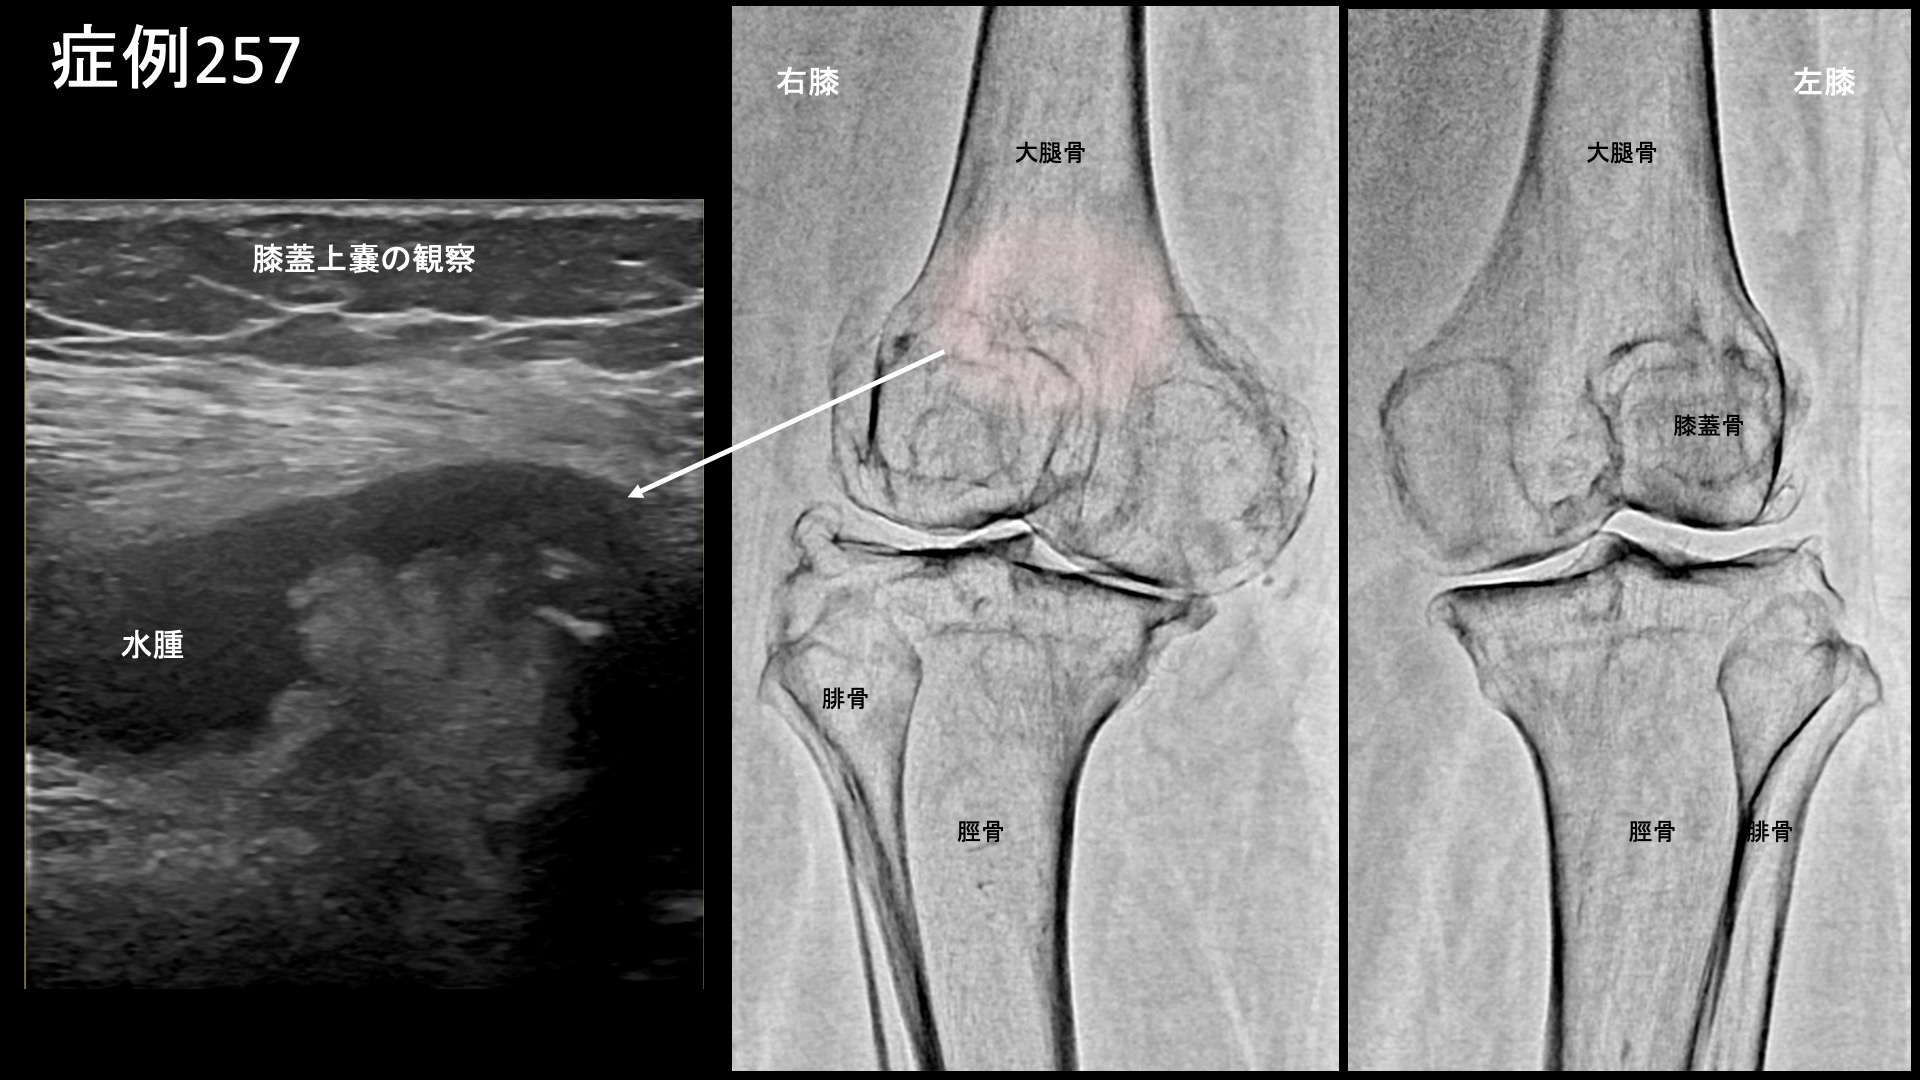

エコー検査では両膝とも水が溜まっており、モヤモヤ血管を反映した異常血流信号も内外にみられました。レントゲン検査では、両膝とも進行性の関節変形(KL分類3程度)を認めたほか、両足関節にも中等度の変形性変化を、足部では扁平足および踵骨棘を認めました。

両膝、両足首、左踵骨内側隆起に一致して圧痛を認めました。以上より、両膝関節および両足関節の変形性関節症、左足底筋膜炎と診断しました。重症度が高く、一定の症状が残存する可能性があること、再発リスクが高いこと、肥満解消や靴・インソールの適正化など総合的に治療していく必要があることなどをご理解いただいたうえで微細動脈塞栓術(運動器カテーテル治療)を受けていただきました。